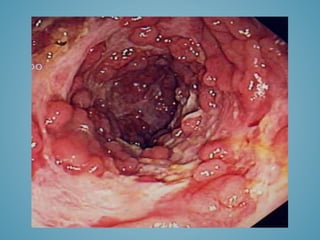

Endoscopy and biopsy

- Can establish the diagnosis

- Estimate the stage and severity of the

disease

- Delinate the treatment options